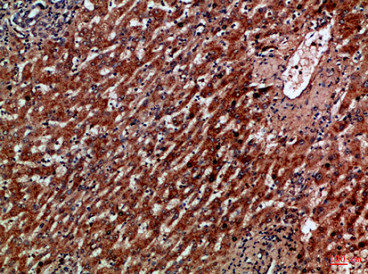

Immunohistochemical analysis of paraffin-embedded Human-liver-cancer, antibody was diluted at 1:100